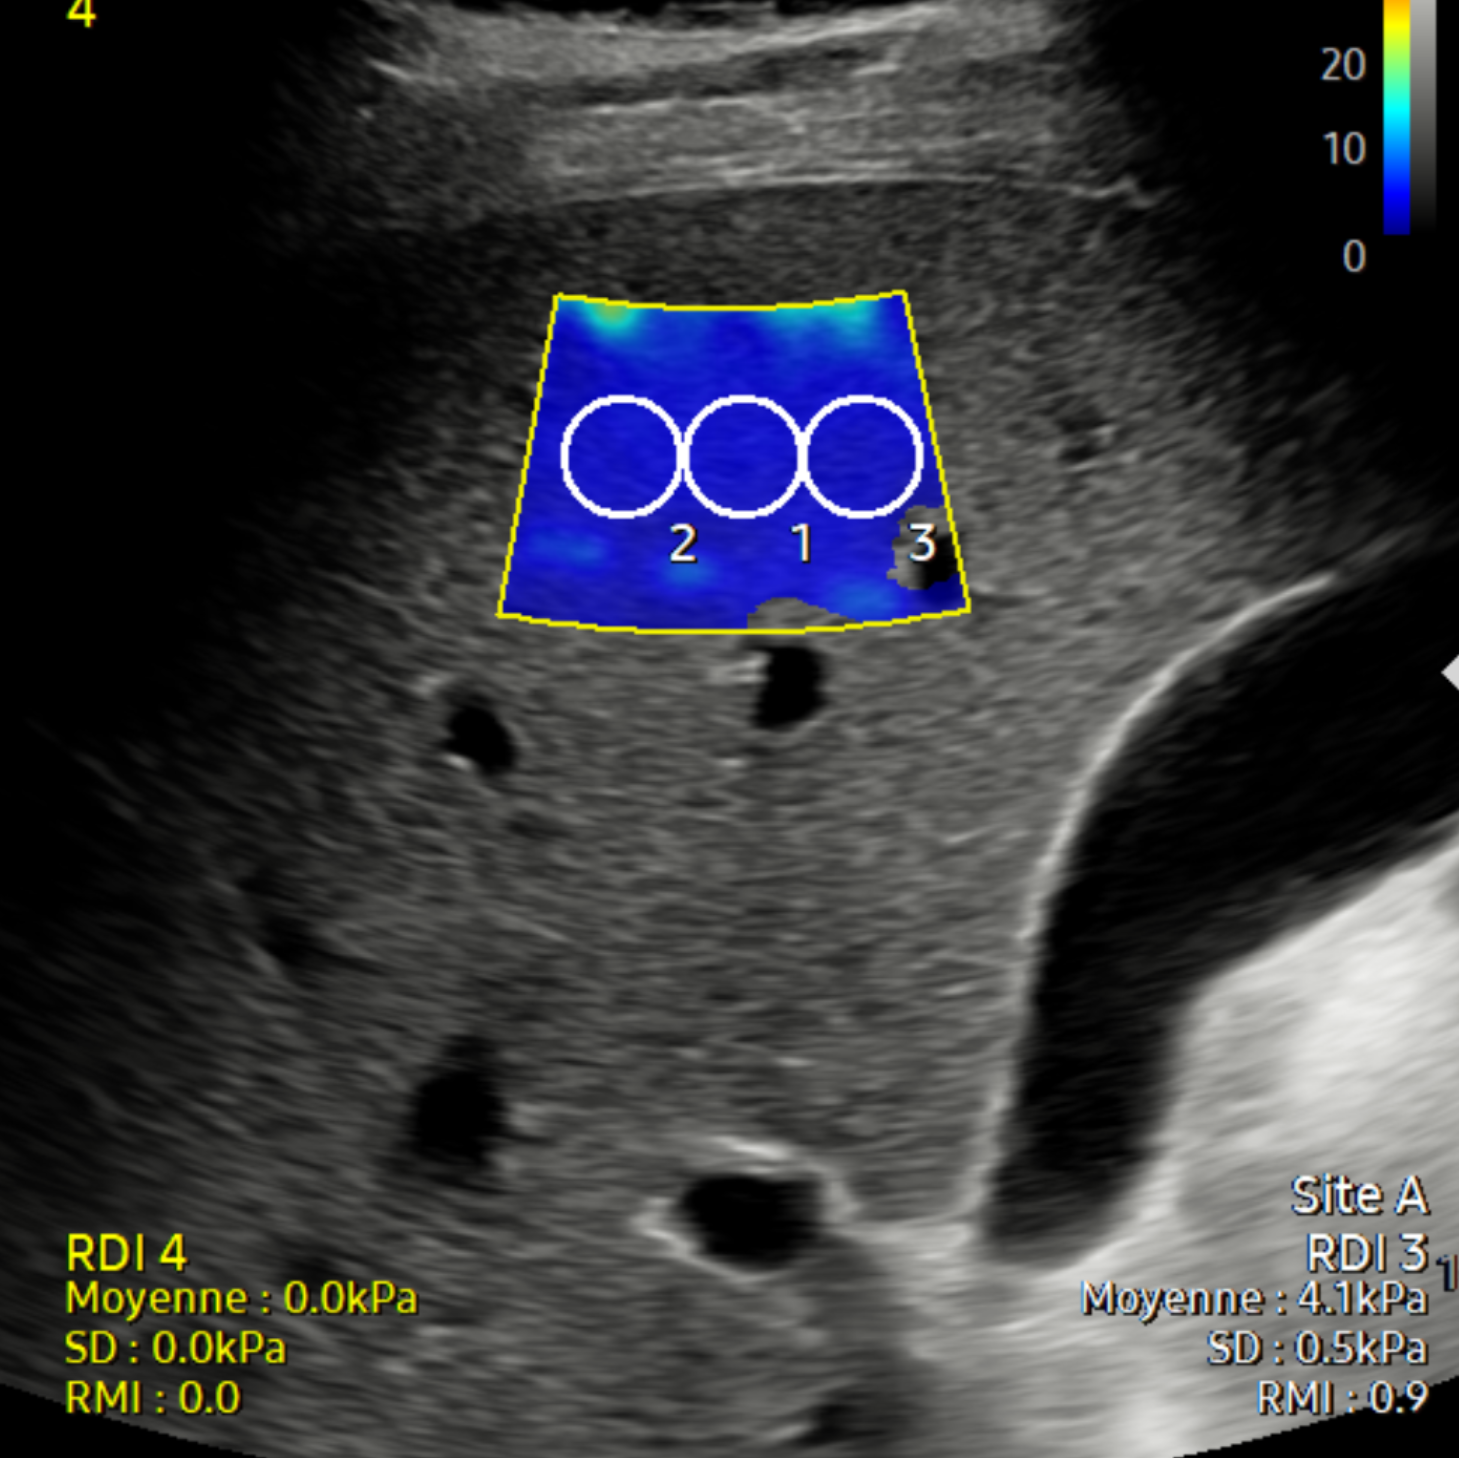

Élastographie hépatique

L'élastographie ultrasonore est une nouvelle modalité d'imagerie qui permet d'imager les propriétés mécaniques des tissus et en particulier leur dureté.

Nous utilisons cet examen surtout pour grader l’élasticité du foie et par là même le degré de fibrose du foie.